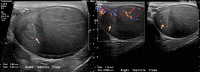

Figure 1. Shows right testicular ultrasonography and doppler ultrasound demonstrating a heterogeneous intratesticular lesion with relatively low echogenicity.